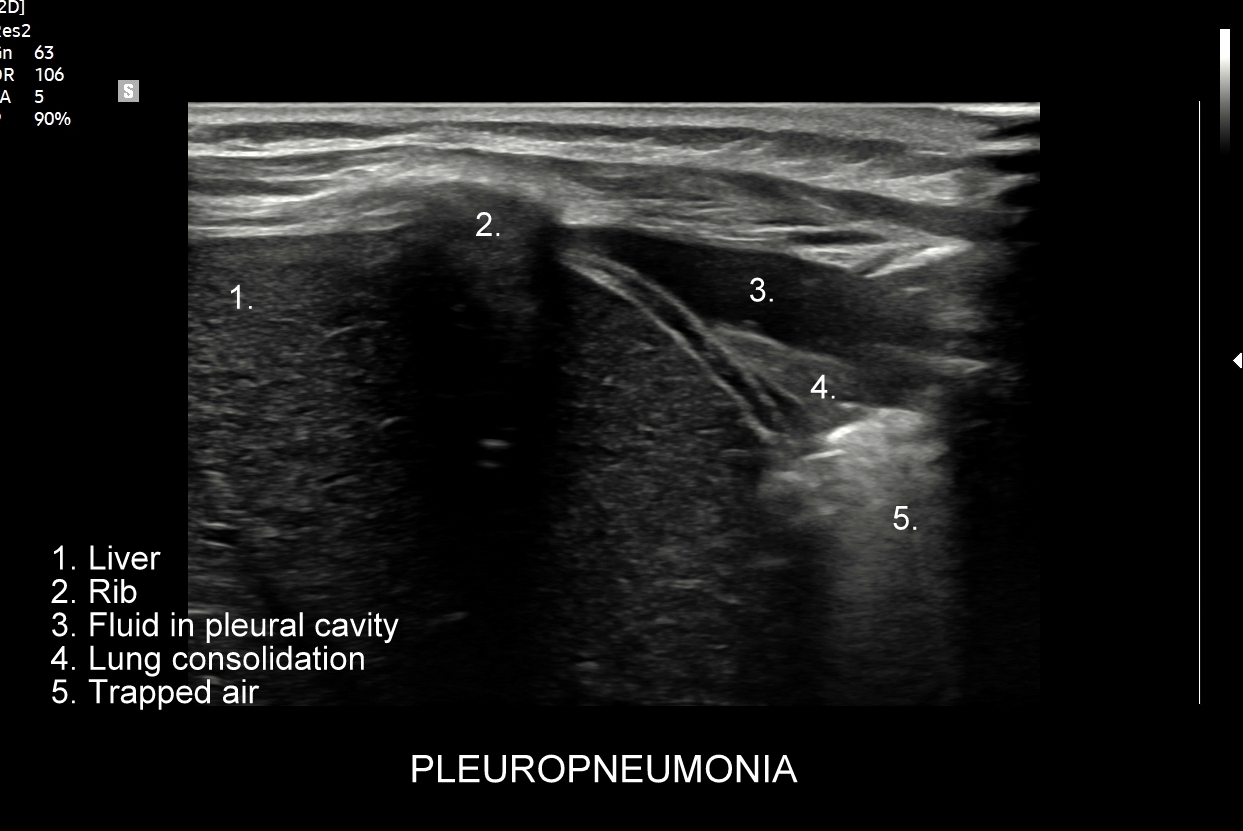

Kluczem do wartościowego zastosowania metody USG w diagnostyce pulmonologicznej jest zrozumienie jej możliwości oraz ograniczeń. USG jest niezwykle czułym badaniem w diagnostyce zapaleń płuc zarówno płatowych, jak i atypowych, np. wywołanych przez Mycoplasma lub Chlamydia. W przypadku zapalenia płuc pojawienie się widocznych zmian sonograficznych wyprzedza wystąpienie fenomenów osłuchowych wykrywanych przy osłuchiwaniu klasycznym stetoskopem. Metoda USG jest również bardzo czuła w diagnostyce chorób opłucnej i jam opłucnowych, takich jak nowotwory opłucnej, odma odma opłucnowa czy płyn w jamie opłucnowej. W rękach doświadczonego lekarza badanie USG może być przydatne w wykryciu zatorowości płucnej, a nawet guzów nowotworowych płuc.